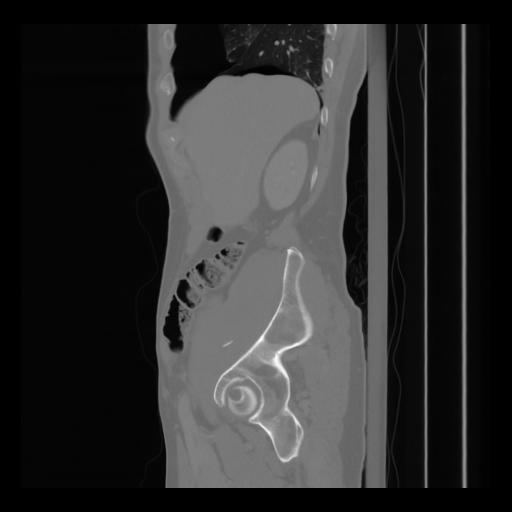

36 CUERPO,CE,Sagittal,3.000,CUERPO,Sagittal,